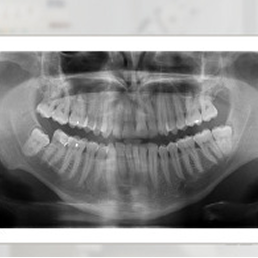

Badanie RTG obrazujące obszar szczęki, żuchwy, stawów skroniowo- żuchwowych oraz zatok szczękowych.

- RTG pantomograficzne (pantomogram) – zdjęcie całej jamy ustnej, obejmujące zęby, szczękę, żuchwę i stawy skroniowo-żuchwowe. Przydatne w ogólnej ocenie stanu uzębienia, przed leczeniem protetycznym, chirurgicznym czy ortodontycznym.